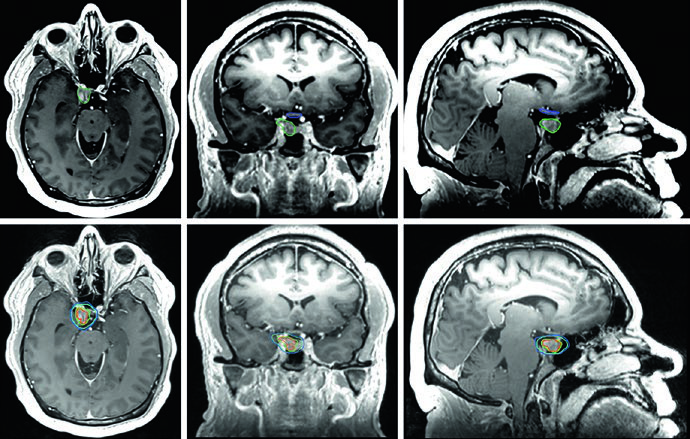

O adenoma secretor de GH da Figura 29.11 demonstra tratamento com SRS a 24 Gy. O tumor toca a margem medial da carótida cavernosa e se estende lateralmente entre as alças da carótida, com envolvimento do seio cavernoso. A dose ao quiasma, nervos ópticos e tronco encefálico permaneceu abaixo de 8 Gy. Na Figura 29.12, o adenoma não secretor mostra invasão do seio cavernoso direito e extensão suprasselar — após ressecção, o tumor residual na sela e no seio cavernoso persistiu.

A Figura 29.13 mostra o planejamento fracionado do mesmo paciente: GTV em coral, CTV com margem de 0,5 cm anatomicamente restrita em teal, PTV com expansão adicional de 0,3 cm. Tronco encefálico, quiasma e nervos ópticos aparecem como OARs delineados. Para macroadenomas, quando a invasão do seio cavernoso é difícil de visualizar, a recomendação é incluir o seio cavernoso inteiro no GTV. Conhecer o tipo de material implantado na sela (músculo, gordura ou retalho de septo nasal) ajuda a diferenciá-lo de tumor residual.